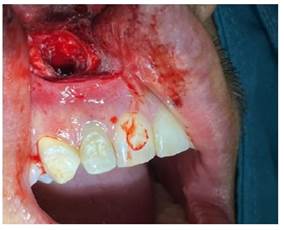

Obteniendo como diagnóstico presuntivo un quiste radicular asociado a la pieza 1.2; se le solicitó al paciente una biometría hemática, con todos los valores dentro de parámetros normales; se realizó el procedimiento quirúrgico de descompresión, por medio de una incisión lineal, el levantamiento del colgajo mucoperiostico y posterior osteotomía a nivel del ápice de la pieza 1.2, hasta descubrir la membrana del quiste (figura 3a), se extiende la ventana con un diámetro de aproximadamente 5 mm compatible con el diámetro del dren que colocaríamos, se realizó una incisión a nivel de la membrana del quiste y se drenó líquido seropurulento, se realiza el lavado mediante el orificio, con suero fisiológico y yodopovidona (Figura 3b).

Figura 3b Se retiro la membrana del quiste a nivel de la ventana ósea y se realizó el drenaje del líquido seropurulento, lavamos a través del orificio con suero fisiológico y yodopovidona.